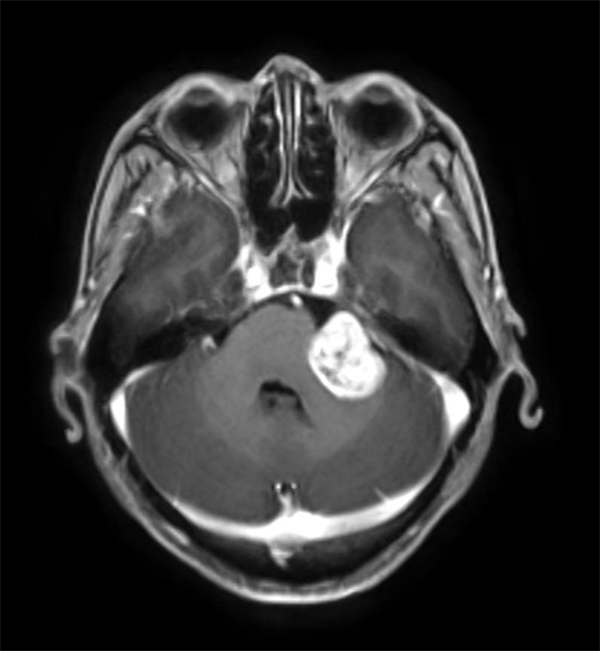

红网时刻新闻11月8日讯(通讯员 李杭键)56岁的张先生近半年来出现左耳听力明显下降,偶尔还有头痛等不适症状,他以为是没有休息好所以没有太在意。近日,张先生左耳听力下降的越发严重,近乎完全听不到声音,且左侧面部麻木伴随口角稍歪斜,意识到事情的严重性,立即到郴州市第四人民医院神经外科就诊。入院完善MRI平扫+增强显示:左侧桥小脑角占位,一枚大小约24mm×26mm×28mm形似“鸽子蛋”的肿瘤卧于患者左侧桥小脑角区,结合张先生的病史、体查及影像学检查,诊断考虑“左侧听神经瘤”。

MRI提示肿瘤形似一枚“鸽子蛋”,生长在患者左侧桥小脑角区。